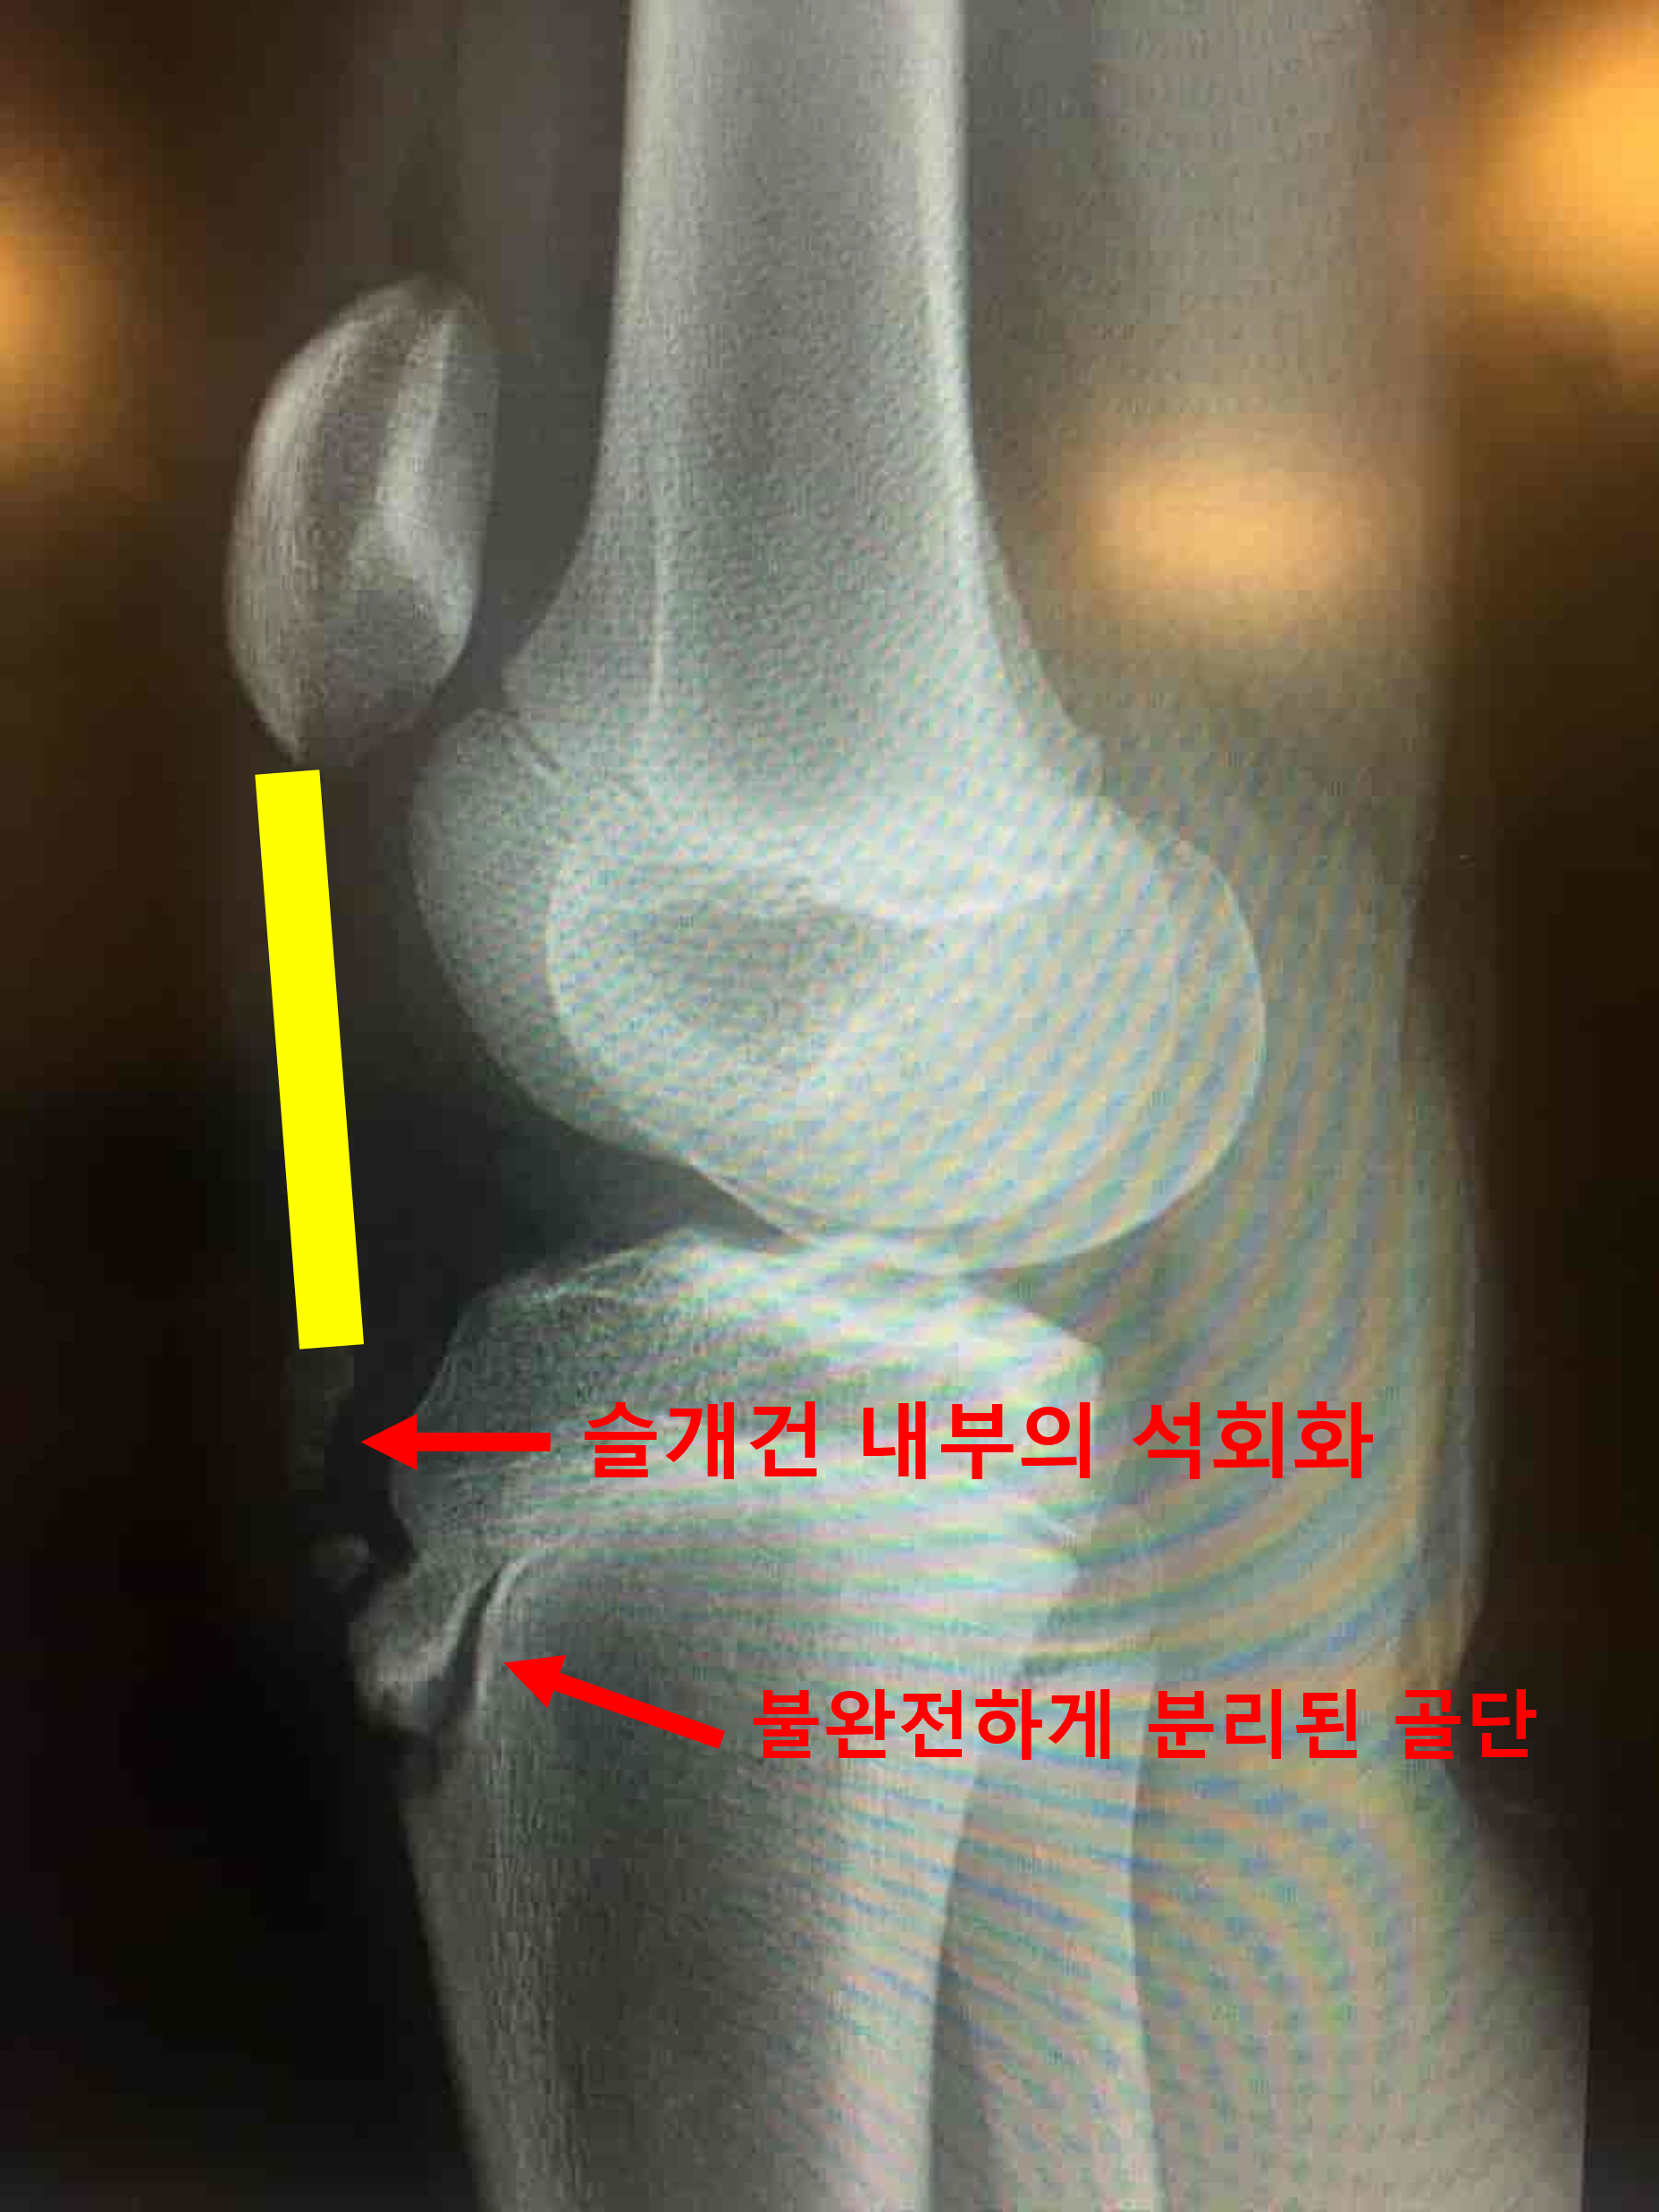

오스굿씨 병의 초기 환자에서는 분리된 골편이 불규칙하게 일부는 붙어있고, 일부는 떨어져나와 보이는 등 균일하지 않은 경계면을 보이게 됩니다. 병변이 진행된 말기에서는 떨어져나온 골편이 명확하게 분리된 것이 보이게되고, 심한 경우 골편이 인대에 견인되어 상방으로 이동해 보이는 경우도 있습니다. 간혹 슬개건 내부에 석회가 낀 것이 보이기도 합니다. (아래 사진 참조,) 이럴 경우에는 외상에 의한 견열 골절 (Avulsion fracture)과 감별이 필요합니다.

완전히 분리된 골단이 보인다.

내부의 석회가 같이 보이는 경우.